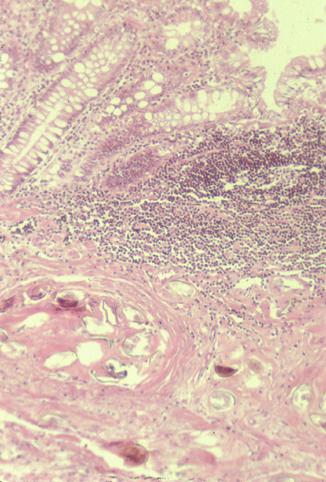

Criteria of Hist.ClassificationMalignant epithelial tumor/Adenocarcinoma

LocationLarge intestine(Colon)/Rectum

Technique, MethodHistology

Macroscopic TypesType 2 Ulcerated type with clear margin/

Size35 - 40

Depth of Tumor Invasionserosa (adventitia)